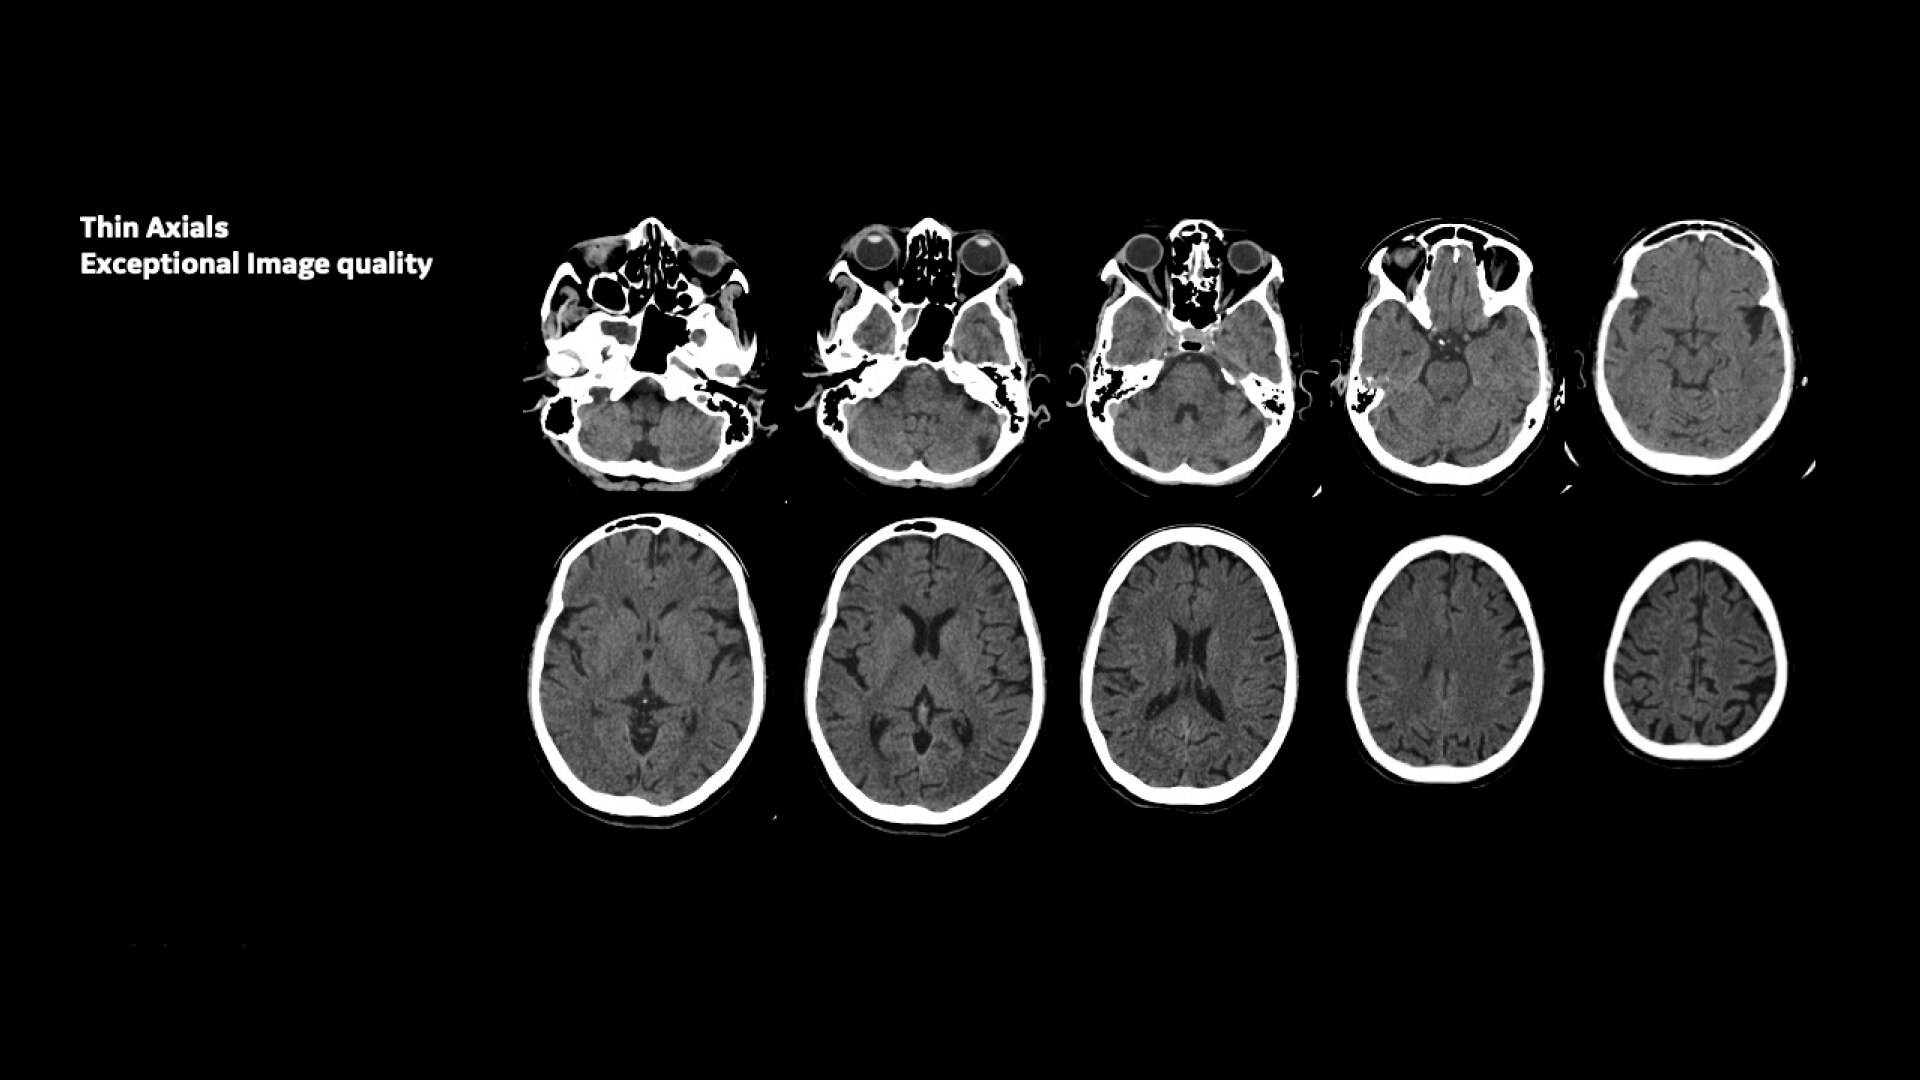

NM/CT 870 DR is a SPECT/CT built for consistent, reproducible quantitation. Improvements to detector performance enable exceptional spatial resolution for SPECT and planar images. It leverages CT-based attenuation and scatter correction along with Evolution⁴ image reconstruction. Ever-increasing computational power enables precise camera calibration for less variation between exams.

Uncompromised image quality